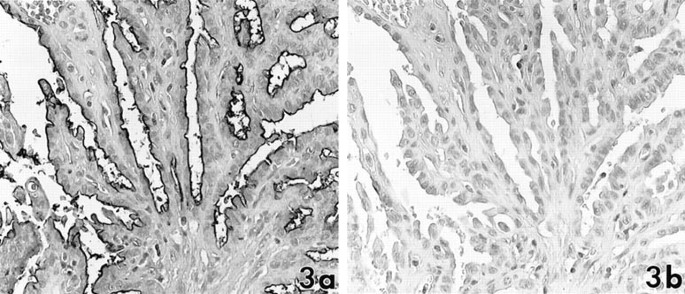

In 43 papillary carcinomas, DU-PAN-2 and CA19–9 were expressed in 42 cases (98%) and 36 cases (84%), respectively. Lea and Leb were occasionally or focally present in 14 (33%) and 21 (49%) cases. The number of tumor cells that expressed DU-PAN-2 was necessarily greater than that expressing CA19–9 and Lea or Leb. The majority of DU-PAN-2–positive cases showed moderate (2+) or marked (3+) staining. Six cases were positive for DU-PAN-2 but negative for CA19–9, Lea, and Leb (Fig. 3). These antigens showed a tendency toward pronounced expressions in invasive elements of tumors in the presence or absence of fibrous stroma (Fig. 4). All of eight follicular variants were positive for DU-PAN-2 but restrictedly stained for CA19–9, Lea, and Leb (Fig. 5). These reaction products were distributed predominantly on the apical membrane of the tumor cells but also occasionally around the cell membrane or the cytoplasm. Colloid substances were rarely stained for these antibodies, and no stromal components expressed the antigens.